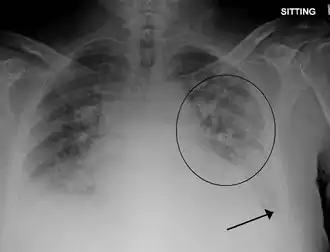

Edema pulmonar (do grego antigo οἴδημα, "transbordar") é o acúmulo de fluido nos pulmões diminuindo a eficiência das trocas gasosas (O2 e CO2) podendo resultar em insuficiência respiratória. É uma das emergências médicas mais frequentes e pode ser fatal em poucas horas. É uma consequência comum de problemas cardíacos, vasculares ou por distúrbios da pressão pulmonar.